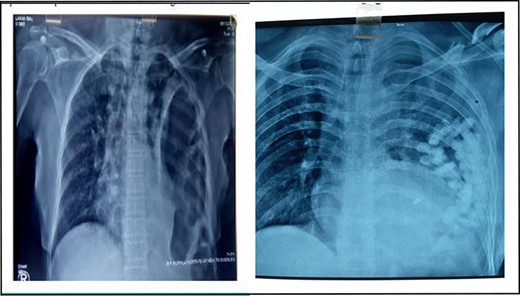

A retrospective analysis was carried out to review records of patients who presented to our department over a period of 3 years from December 2017 to January 2020. All patients with diaphragmatic hernias were included in the study. Preoperative diagnosis of diaphragmatic hernia was based on history, clinical examination and radiological investigations (chest X-ray and CT) (Figs 1 and 2).

Axial section showing collapsed left lung with bowel in left thoracic cavity.